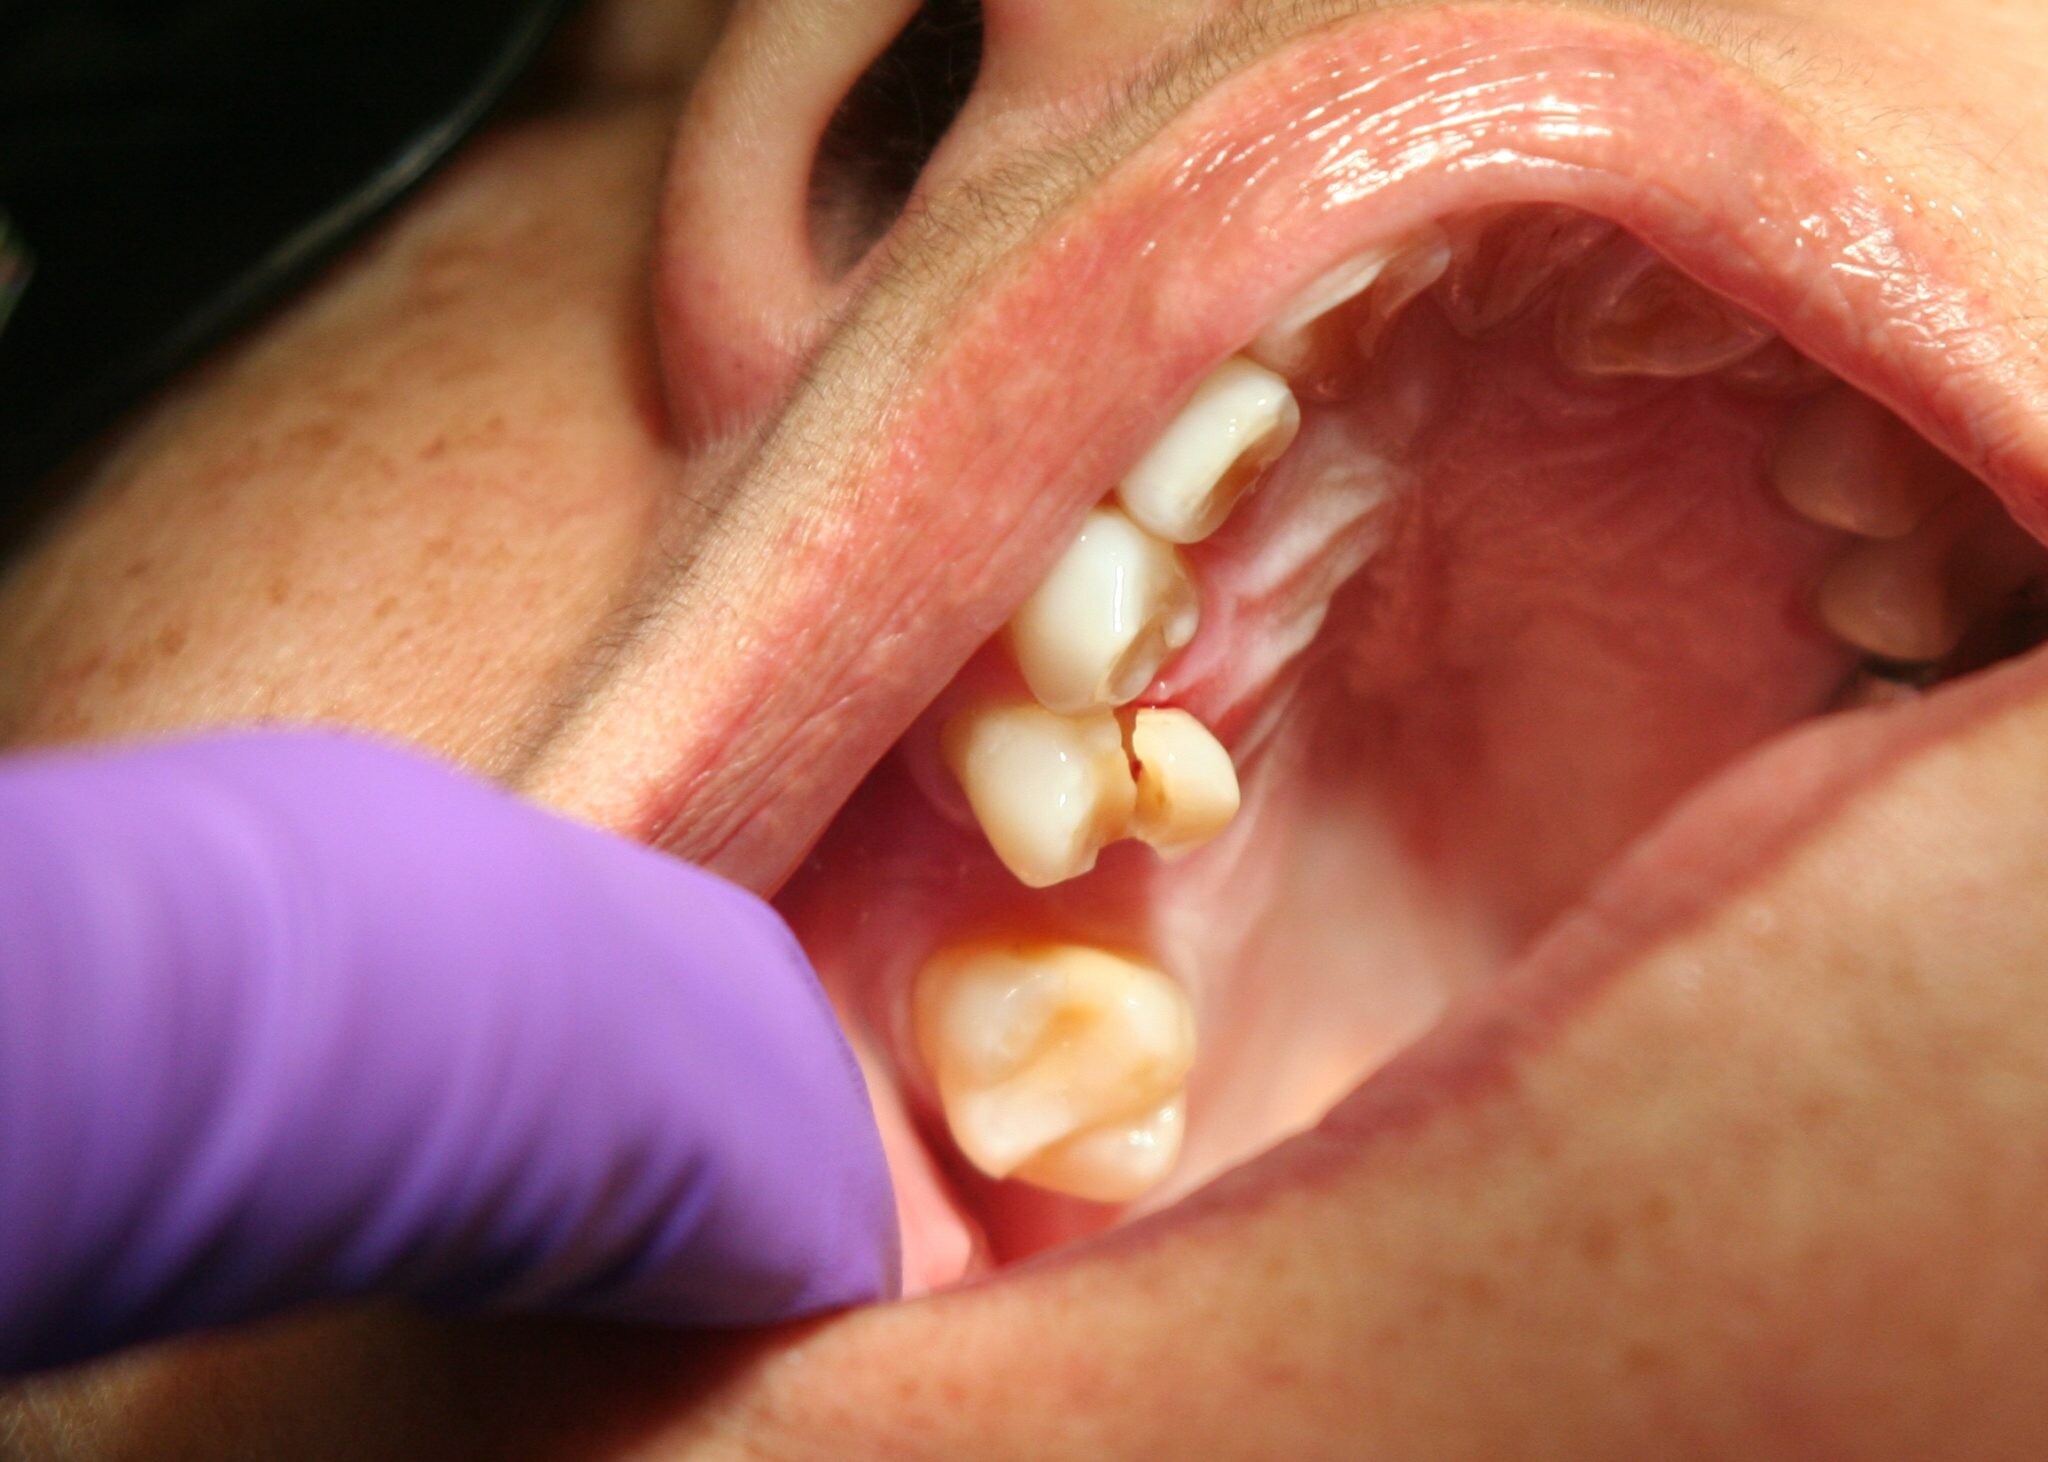

In some cases, jaw pain on one side can indicate underlying oral health problems. Some common issues that cause jaw pain are cavities, an abscessed tooth, gum disease, tooth decay, growth of wisdom teeth, missing or crooked teeth, and clenching or grinding your teeth.

Tooth decay

As tooth decay progresses, it can reach the softer inner layers of the tooth, called dentin and pulp, resulting in sensitivity to hot, cold, or sweet foods and drinks and eventually leading to a toothache. If left untreated, tooth decay can result in an abscess, a painful infection at the root of the tooth that can cause severe pain and swelling. Adhering to your routine dental check-ups, practicing good oral hygiene, and eating a healthy diet can help prevent tooth decay and the resulting toothache.

Tooth fracture

A tooth fracture can expose the sensitive nerves and blood vessels inside your tooth, leading to pain and discomfort. The severity of your discomfort can vary, depending on the extent and location of the fracture. A small crack or chip may only cause mild discomfort, while a larger fracture may result in severe pain and sensitivity to hot and cold foods and drinks. In some cases, a tooth fracture can also lead to infection, further exacerbating the pain and requiring immediate dental treatment.